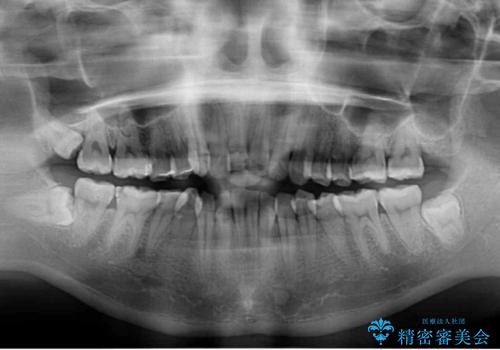

- 転倒により前歯の一部が欠けてしまったとのことで来院された患者様です。

神経が保存できる歯、神経を除去しなければならない歯、抜歯が必要な歯があり、ブリッジやインプラントなどによる治療を提案しました。

元々歯並びが気になっていたとのことで、前歯の治療を行うことを契機に矯正治療も行うこととしました。

本来であれば積極的に小臼歯を抜歯して口元を下げても良いのですが、前歯を1本抜歯しないといけなくなったため、非抜歯矯正をインビザラインを用いて行うこととしました。

補助装置により上顎歯列を遠心移動させたため、非抜歯でしたが口元の突出感をある程度改善させることができました。